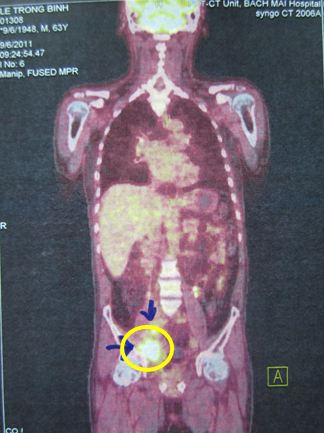

Bệnh nhân được chỉ định chụp PET/CT toàn thân có mô phỏng với kết quả hai khối tổn thương tăng hấp thu FDG mạnh với SUV tăng rất cao vùng hố chậu bên phải:

Hình ảnh PET/CT cắt dọc: Vùng tổn thương trong vòng màu vàng

Dựa vào lâm sàng, xét nghiệm và các tổn thương trên hình ảnh PET/CT chúng đưa ra chẩn đoán xác định: Nhiễm trùng tiết niệu, suy thận cấp trên bệnh nhân bị ung thư bàng quang, sau phẫu thuật cắt toàn bộ bàng quang, giai đoạn T4N2M0